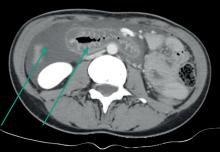

D’après : Bouvard B, Legrand E. Ostéoporose : encore trop ignorée ! Rev Prat Med Gen 2025;39(1100);381-91.